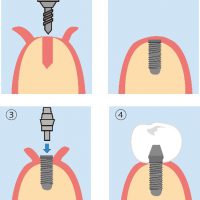

インプラントについてご質問を受けることがあります。その中で当院がもっとも大事だなと思うものをピックアップしました。インプラントを手術するにあたり、歯医者が一番頑張らないといけないのが、インプラントのポジションです。インプラントの位置です。これだけは一度インプラントをお口に入れてしまったら、変更することができません。一回の勝負になります。ですから慎重に、考えに考えて埋入する必要があります。考えて埋入しても手がぶれてしまっては元も子もないです。

そんなとき、役に立つのがこのサージカルガイドです。当院ではSMOPを使っています。SMOPはSwissmeda Online Planningの頭文字をとったものです。スイスのSwissmeda社が開発したクラウドベースのインプラントガイドシステムで、CTデータをもとに精密な3Dシミュレーションを行い、患者一人ひとりに最適なサージカルガイド(ステント)を作製することが可能です。

- 高精度なシミュレーション:CTデータと口腔内スキャンデータを統合し、インプラントの最適な埋入位置や角度を事前にシミュレーションできます。

- サージカルガイドの作製:シミュレーション結果をもとに、3Dプリンターで高精度なサージカルガイドを作製し、手術時の正確なインプラント埋入をサポートします

インプラント手術にSMOPを入れました。

インプラントがセットした後の写真が以下の通りです。

スクリューリテインで素晴らしい結果となりました。